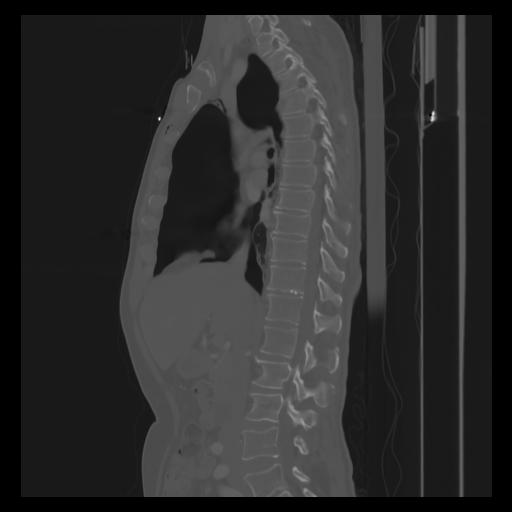

30 CUERPO,CE,Sagittal,3.000,CUERPO,Sagittal,